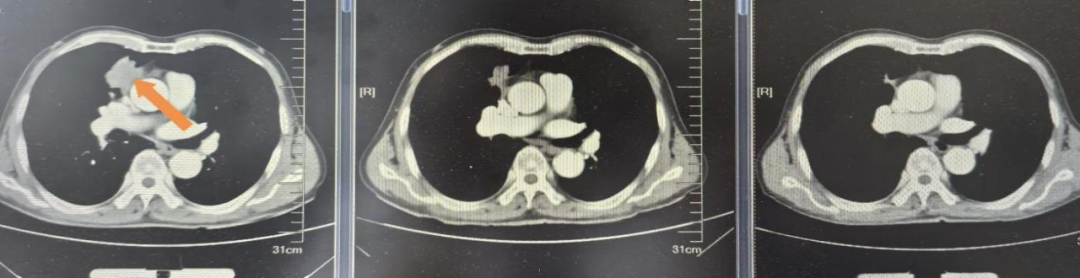

患者男,79岁,2025.5月以“右下肢无力1月”为主诉入院,检查头MRI+C:左侧额叶异常强化,周围片状水肿信号,符合转移瘤;肺CT+C:右肺上叶纵隔旁肿物,可疑恶性。行肺穿刺活检病理诊断为肺腺癌伴少数鳞状分化,免疫组化PD-L1(22C3)TPS=70%,基因检测:KRAS G12V突变,临床分期:cT2aN0M1b IVA期,PS评分1分。恰逢依沃西单抗单药获国家药品监督管理局批准于PD-L1表达阳性(PD-L1 TPS≥1%)的局部晚期或转移性非小细胞肺癌的一线治疗适应症,2025年6月行依沃西单抗单药治疗4周期后患者右下肢无力症状明显缓解,10月复查头增强MRI额叶周围水肿带消失,疗效评价持续PR,治疗期间出现不良反应为恶心呕吐II级,对症止吐治疗后好转,目前持续治疗中。

依沃西单抗4周期疗效对比